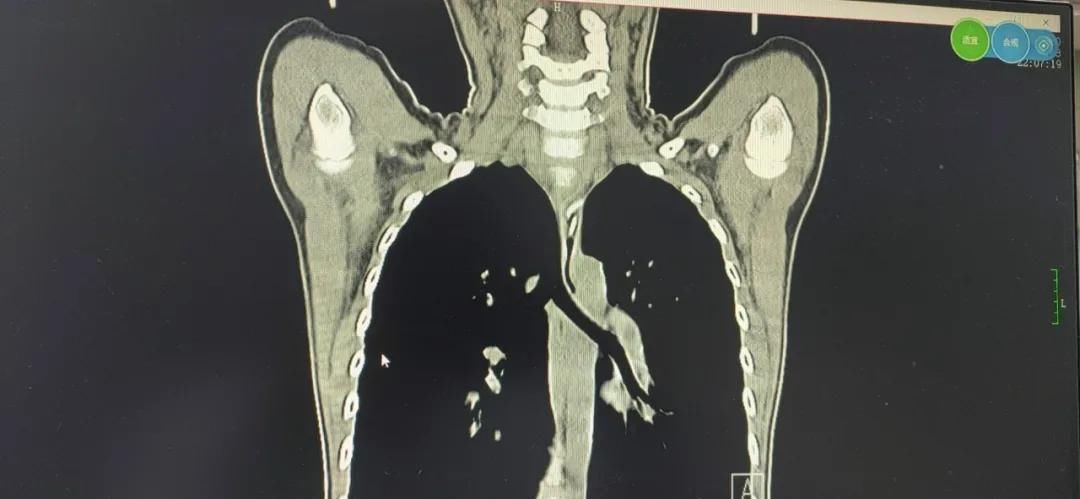

一根鸡骨头卡喉咙 竟让她差点瘫痪

小小一根鸡骨头卡喉咙,竟让她差点瘫痪

中年妇女不慎将鸡骨头卡在喉咙,辗转7家